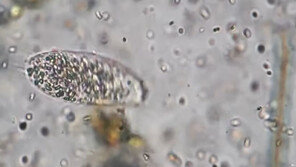

지난달 중국에서 부모와 함께 온천에 다녀 온 5세 여아가 ‘뇌 먹는 아메바’로 불리는 파울러자유아메바(Naegleriafowleri)에 감염 돼 사경을 헤매고 있다는 소식이 이달 초 전해진 데 이어, 최근 미국에서는 같은 이유로 치료를 받던 어린이가 사망했다.복수의 현지 매체에 따르…